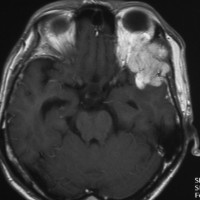

1984年 19歳の時に,松果体のジャーミノーマに全脳照射45グレイで治療されました(左CT)。1997年左蝶形骨縁にヘマンジオペリサイトーマが発生しました(中央と右のMRI)。手術で全摘出しましたが4年後,2001年に脊髄に播種再発してつらい経過を辿りました。眼窩壁を破る典型的なヘマンジオペリサイトーマの像で,放射線誘発髄膜腫との鑑別がとても大切なものです。

左側の画像は照射後再発を手術摘出後です,数ヶ月で再燃しています,かなり早い増殖速度で再発してきて取りきれません